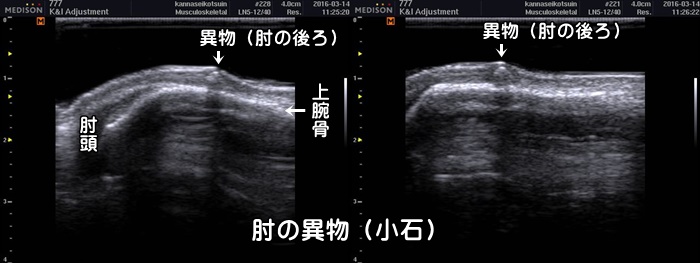

体内の異物

自転車で転倒して肘を擦りむき負傷し病院で処置されました。しばらくしてから肘の後ろに膨らみを自覚。押すと痛みがあり、肘をついたりしても痛みがある。エコーでは皮下に異物らしきものが描出されています。病院でしばらくは経過観察と言われましたが受傷後1年してから除去手術。中の異物は傷口から入った小石でした。